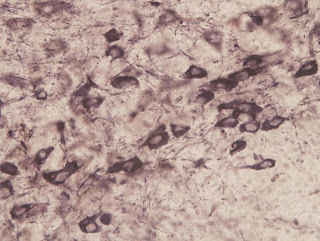

experimental pictures out of my hands

Being a graduate student engaged in neuroscientific research, I earnestly studied the courses related to my majoring and set my hands on experiments. As a cooperation project of department of immunology and my supervisor, I chose the mouse model of PD and investigated the role of complement, a component of innate immune system, in the pathogenesis of MPTP induced neurodegeneration of dopamine neurons in Snpc, harnessing complement 3 knock out mice. It was a challenging task in our lab since no one has ever done this before, involving the making of the injury model and large amount of article reading. Although I failed to obtain a positive result in the main project, a parallel idea did work, which provide the clue for me to proceed and finally composed a paper which is just the English publication in my CV(it is also attached to the letter, if you don’t mind).